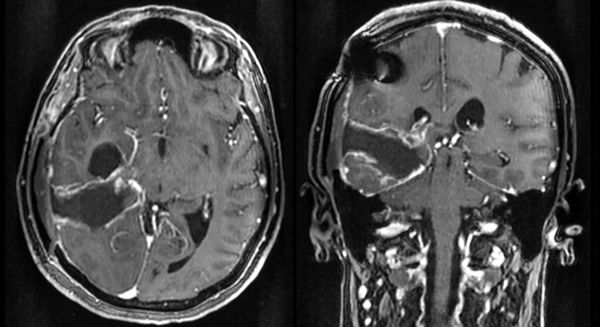

Se realizaron controles periódicos, con buena evolución de las funciones cognitivas, aunque el déficit visual persistió, presumiblemente por isquemia de un segmento del área visual primaria (dependiente de la cerebral posterior) o por daño a las radiaciones ópticas temporales. Se efectuó RM de control a los dos meses de la intervención, objetivándose una óptima resección tumoral (Figura 3).

Figura 3. RM con gadolinio en secuencia T1, corte axial a la izquierda, coronal a la derecha. Se observa una buena resección, con un posible remanente tumoral residual hacia la porción más medial.

En sucesivos controles la paciente presenta un deterioro de su estatus previo, con signos clínicos de hipertensión endocraneana (cefalea y episodios aislados de náuseas y vómitos), por lo que se indica una nueva RM. La resonancia es realizada a los cinco meses de la intervención quirúrgica (Figura 4).

Figura 4. Se observa una importante recidiva de la masa tumoral con efecto de masa y secuestro ventricular temporal derecho.